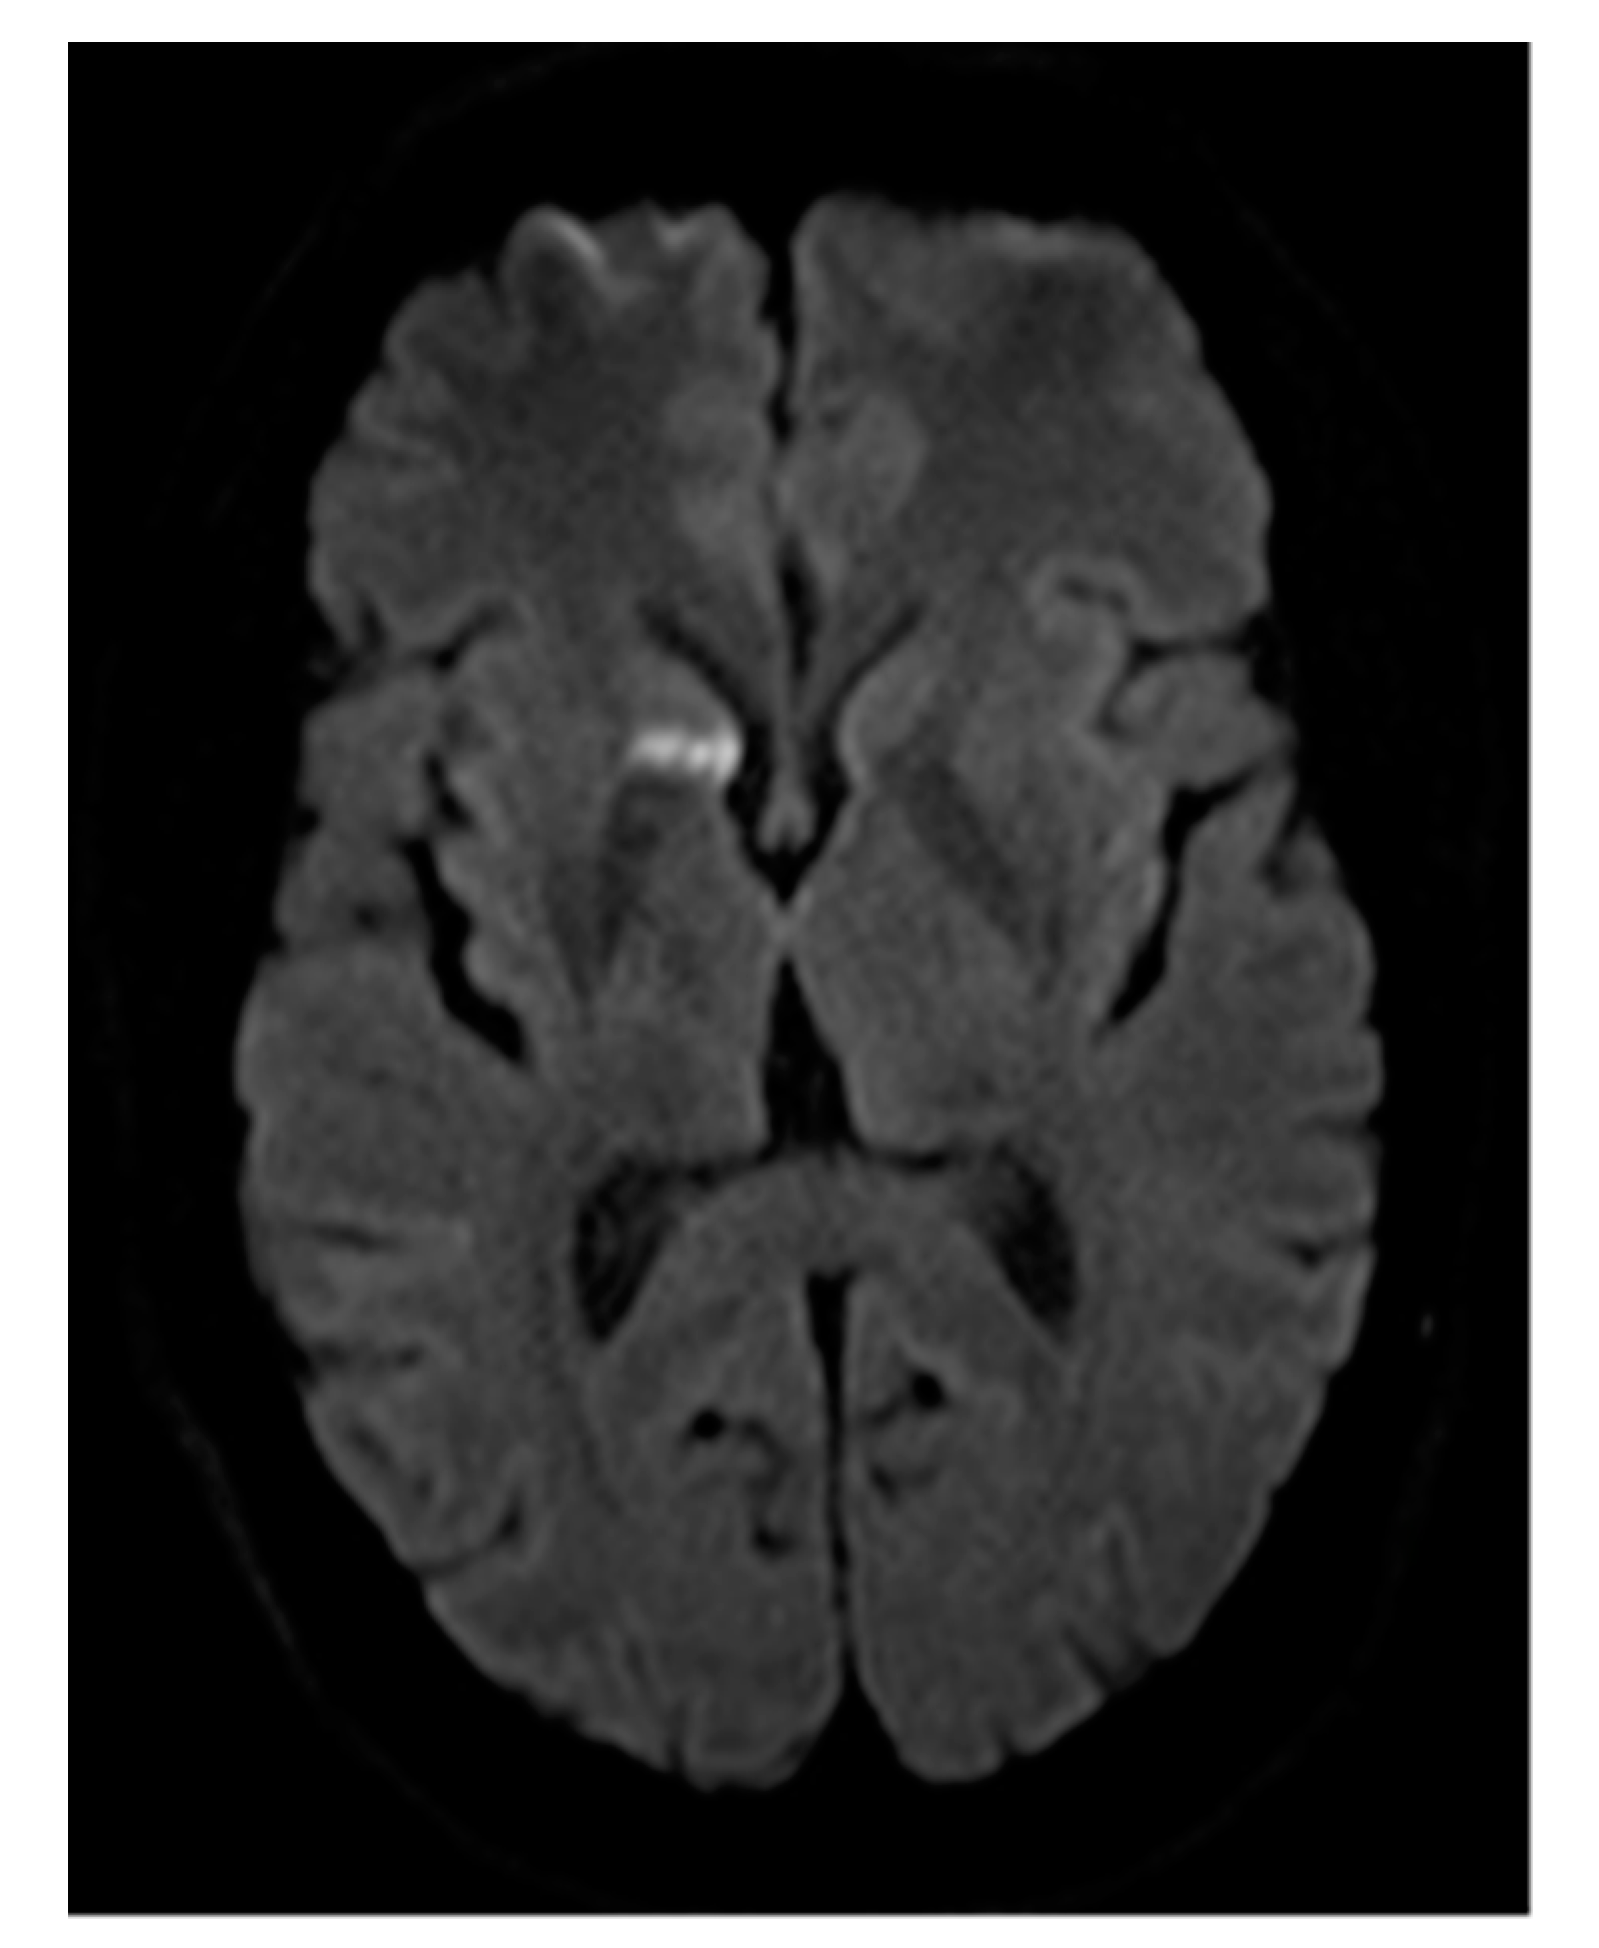

Figure 3. (ac) Re-perfused PAVM after previous treatment elsewhere. Contrast-enhanced MRA (a) shows two large, re-perfused PAVMs (arrows) with early enhancement of the draining vein. In (b) the DSA of one re-perfused PAVM is shown, depicting insufficient dense packing of coils resulting in reperfusion of the vessel. No guide wire should be used, since small thrombi from the coils might be mobilized and lead to systemic emboli. In (c) the second re-perfused PAVM is demonstrated, showing only small coils at the wall of the vessel. Embolization was performed proximal to the treated vessel segment to avoid possible migration of the coils.